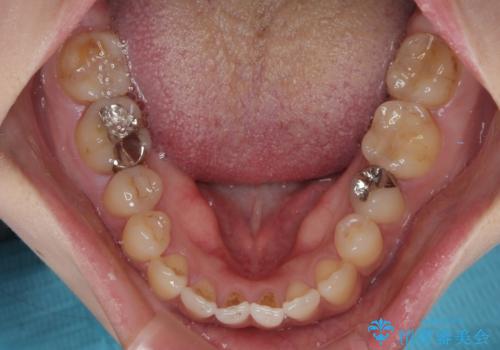

開咬をワイヤー装置で矯正治療

- 上下前歯が非接触となっている咬み合わせを気にして来院された患者様です。

開咬となっている原因の大半は、舌の突出癖によるものであるため、治療開始前から舌のトレーニングを開始し、スムーズに治療が進むようにしました。

開咬の方は、インビザライン矯正治療が適していますが、自己管理の煩わしさと、転勤の可能性がありマウスピース矯正であると通院しなくなるだろうとのことで、ワイヤー装置にて矯正治療を行うこととしました。